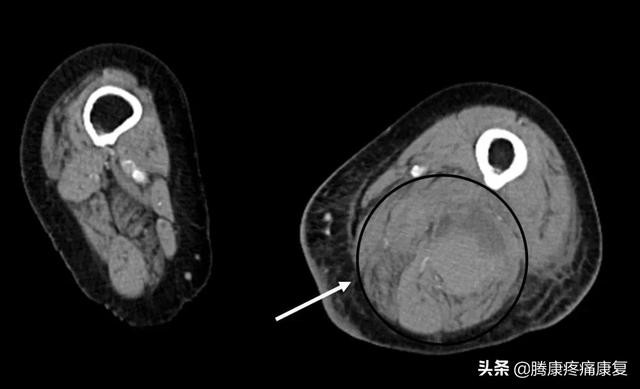

肌与骨骼的脓肿不常见,它们可由邻近的骨或软组织感染扩展所致或经血路播散引起,通常是由金黄色葡萄球菌引起的。

经常是一块肌肉或是大腿肌肉群,通常会引起臀部抽筋,随着感染的进展,还会出现发烧,肌肉无力、肿胀,还会在肌肉内可见脓肿。

下肢PET/CT图像显示腓肠肌内出现大量坏死性肿块。每一个直径约5厘米,有15个亨氏单位,周围环绕着一圈明显的FDG嗜好。这两种方法都与腓肠肌脓肿或局灶性肌肉液化最为相容。沿右胫前肌走行可见进一步的FDG摄取。右中足和左前足外侧有明显的FDG亲和力。右臀肌组织明显增大,边缘模糊,也显示中度至明显的FDG亲和力。右腘绳肌群内有中度FDG摄取。在双膝周围的滑膜分布中观察到明显的FDG摄取。

如果不及时治疗,感染还会继续扩散至其他器官,例如心脏、肺和大脑。